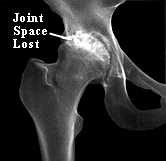

An X-Ray and Illustration Showing an Arthritic Hip Joint

OSTEOARTHRITIS AND RHEUMATOID ARTHRITISOsteoarthritis mainly damages the joint cartilage, but there is often some inflammation as well. It usually affects only one or two major joints (usually in the legs). It does not affect the internal organs. The cause of hip osteoarthritis is not known. It is thought to be simply a process of wear and tear in most cases. Some conditions may predispose the hip to osteoarthritis, for example, a previous fracture that involved the joint. Growth abnormalities of the hip (such as a shallow socket) may lead to premature arthritis. Some childhood hip problems later cause hip arthritis (for example, a type of childhood hip fracture known as a Slipped Epiphysis; also Legg-Pertheís Disease). In osteoarthritis of the hip the cartilage cushion is either thinner than normal (leaving bare spots on the bone), or completely absent. Bare bone on the head of the femur grinding against the bone of the pelvic socket causes mechanical pain. Fragments of cartilage floating in the joint may cause inflammation in the joint lining, and this is a second source of pain. X-rays show the ìjoint spaceî to be narrowed and irregular in outline. There is no blood test for osteoarthritis.